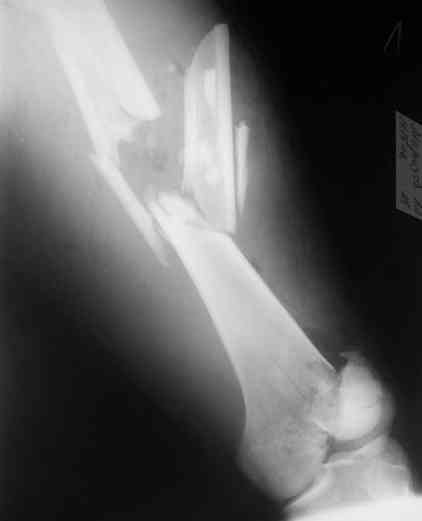

Re: Перелом диафиза и мыщелка бедра

Alexander Chelnokov 26 Октябрь 2006, 23:39

То есть оперировать уже можно. Какие планы обсуждаются на месте? Что именно вызывает разногласия? Что доступно в Ваших условиях?

Лучше бы уточнить характер повреждения наружного мыщелка бедра, есть ли его фронтальное раскалывание. Мы бы сделали репозицию мыщелка (если получится, то закрыто) с фиксацией спонгиозными винтами.

Не получится закрыто - наружный парапателлярный доступ, открытая репозиция, винты. И сделали бы закрытый интрамедуллярный остеосинтез бедра антгерадно. Если есть возможность, лучше использовать гвоздь, который позволит провести винты через мыщелок, т.е. очень близко к

дистальному концу.

Вполне возможен и ретроградный остеосинтез бедра, особенно если все-таки придется открывать сустав.